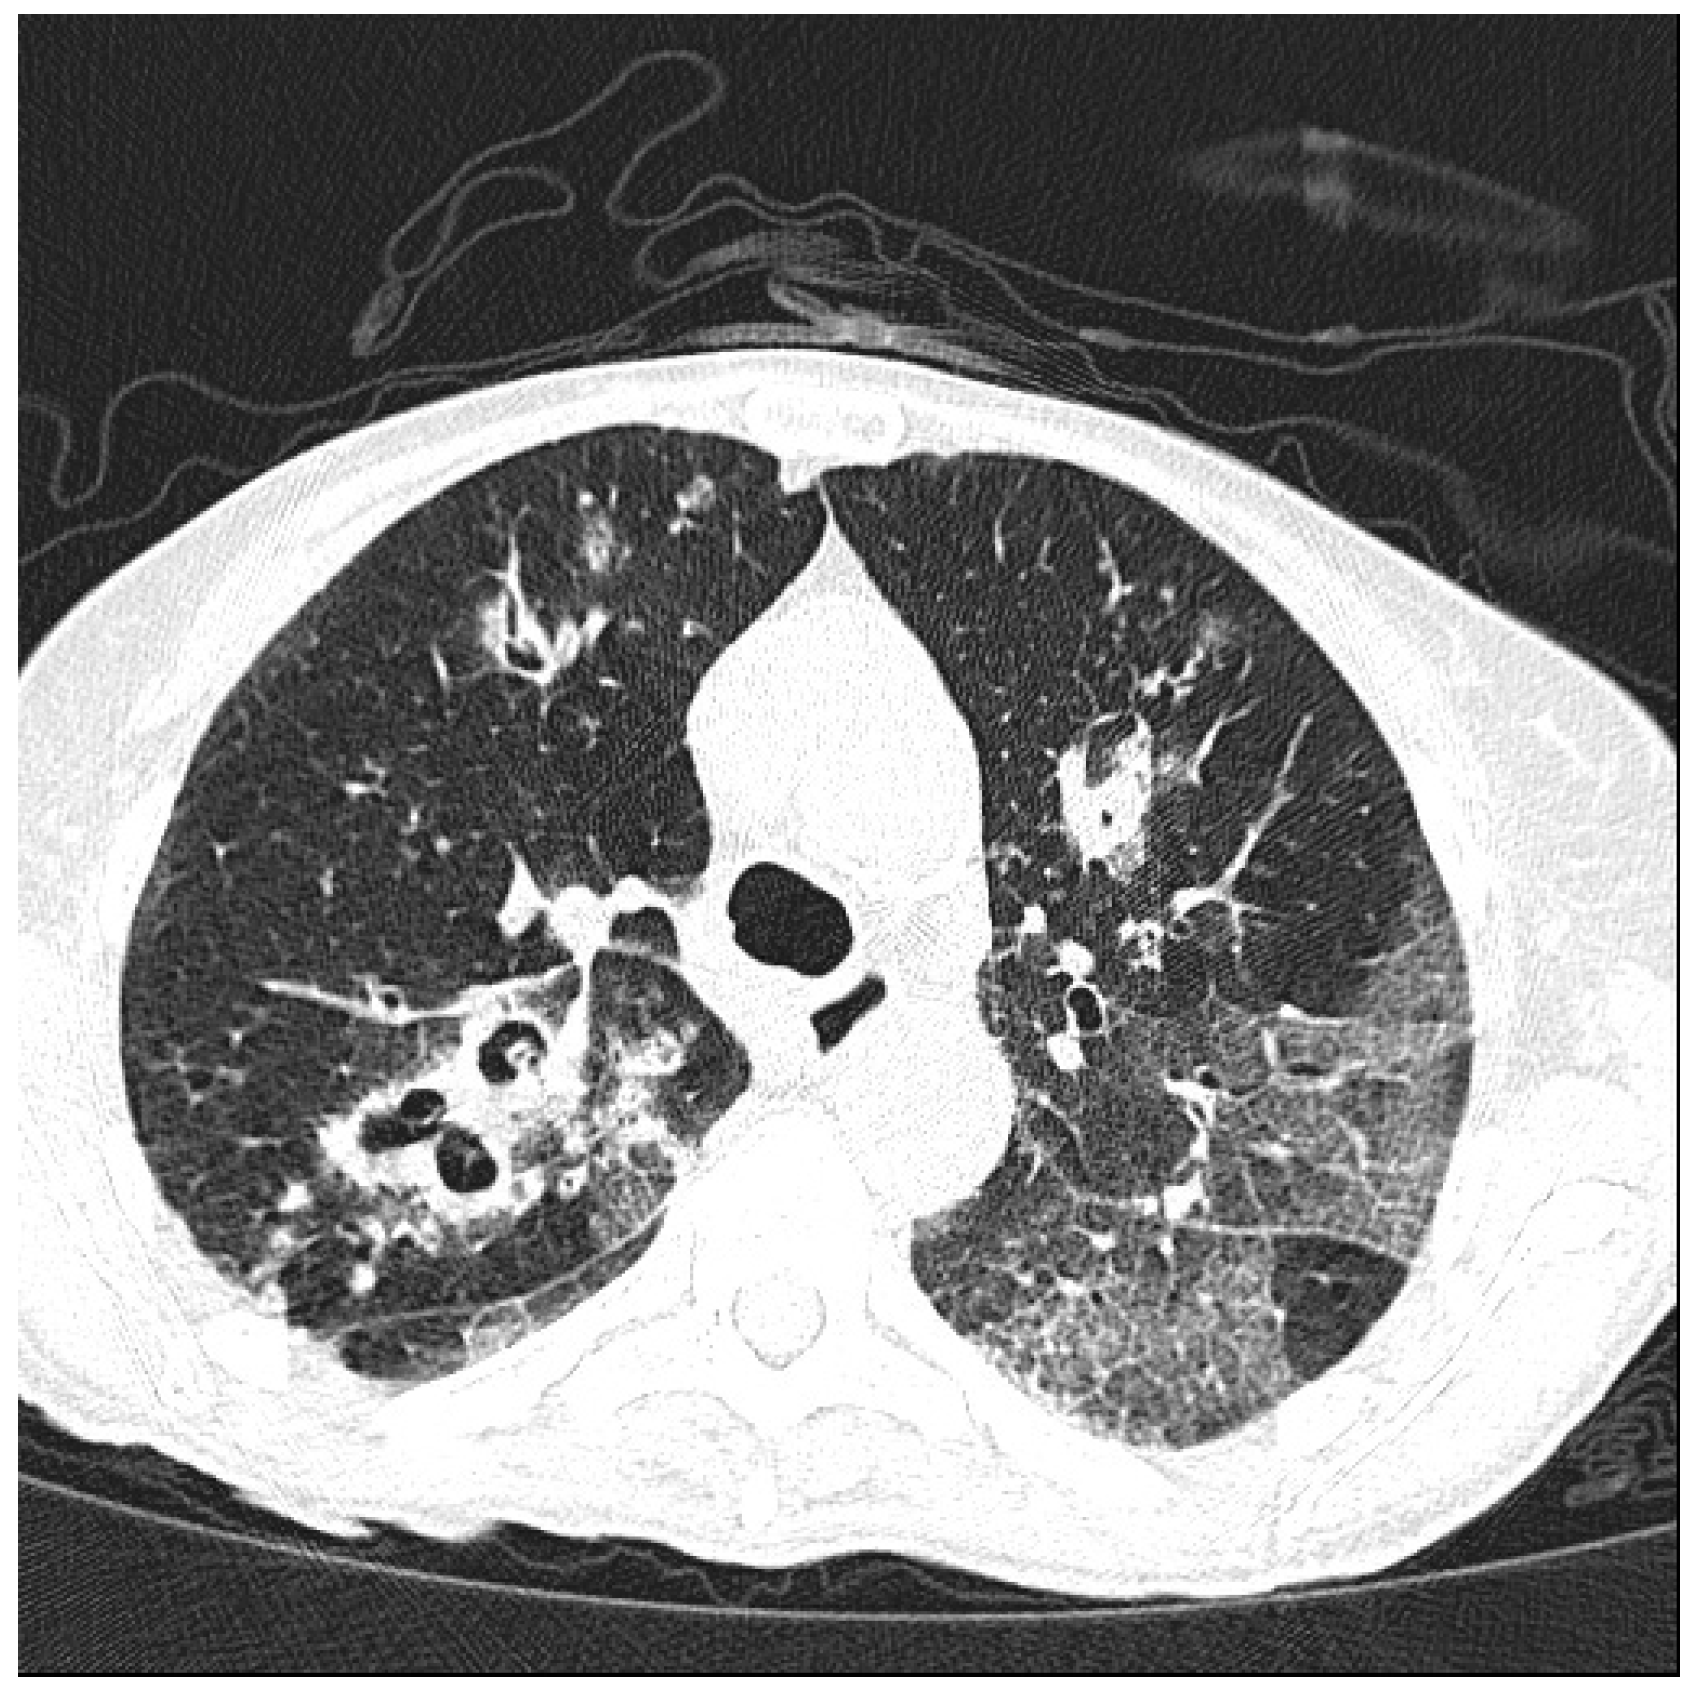

- Tokuda, H.; Sakai, F.; Yamada, H.; Johkoh, T.; Imamura, A.; Dohi, M.; Hirakata, M.; Yamada, T.; Kamatani, N.; Kikuchi, Y.; et al. Clinical and radiological features of Pneumocystis pneumonia in patients with rheumatoid arthritis, in comparison with methotrexate pneumonitis and Pneumocystis pneumonia in acquired immunodeficiency syndrome: A multicenter study. Intern. Med. 2008, 47, 915–923. [Google Scholar] [CrossRef] [PubMed]

- Mu, X.D.; Jia, P.; Gao, L.; Su, L.; Zhang, C.; Wang, R.G.; Wang, G.F. Relationship between Radiological Stages and Prognoses of Pneumocystis Pneumonia in Non-AIDS Immunocompromised Patients. Chin. Med. J. (Engl.) 2016, 129, 2020–2025. [Google Scholar] [CrossRef] [PubMed]

- Demirkazik, F.B.; Akin, A.; Uzun, O.; Akpinar, M.G.; Ariyürek, M.O. CT findings in immunocompromised patients with pulmonary infections. Diagn. Interv. Radiol. 2008, 14, 75–82. [Google Scholar] [PubMed]